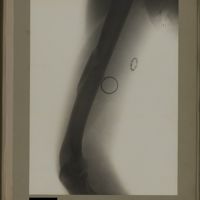

0115 - Page 3 - [Radiographie de l'humérus]0115 - Page 3 - [Radiographie de l'humérus]

0120 - Page 8 - [Radiographie de l'humérus]0120 - Page 8 - [Radiographie de l'humérus]